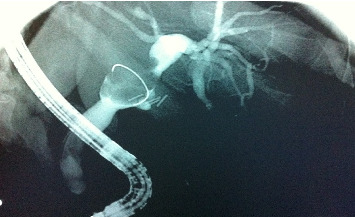

Background: Cholangiocarcinoma (CCA) is a rare malignancy of the biliary epithelium, accounting for approximately 3% of gastrointestinal cancers. The clear-cell variant of CCA is rare, with only nine documented cases worldwide. This case report describes a unique presentation of clear-cell intrahepatic (or peripheral) cholangiocarcinoma (ICC), highlighting its clinical course, histopathological features, and management. Case Presentation: A 56-year-old female with no significant medical history presented with postprandial right upper quadrant and epigastric pain. Following an initial diagnosis of gallbladder stones, laparoscopic cholecystectomy was performed. However, persistent epigastric pain, nausea, and vomiting led to further evaluation, revealing a 2.7 × 2.5 cm mass in the gallbladder bed compressing the common bile duct with associated intrahepatic biliary dilation. Endoscopic retrograde cholangiopancreatography confirmed the findings, and the patient underwent a left hemihepatectomy with radical choledectomy and biliary reconstruction. Histopathology demonstrated clear-cell ICC. Postoperatively, the patient received adjuvant chemotherapy and remained disease free at 14 months' follow-up. Methods: A systematic review and meta-analysis were conducted according to PRISMA guidelines and the Cochrane Handbook. A comprehensive search of PubMed and SCOPUS was performed without restrictions until December 2024 to identify case reports and case series of clear-cell CCA. Data on clinical presentation, diagnostic findings, treatment modalities, and outcomes were extracted and analyzed. The quality of included studies was assessed using the Joanna Briggs Institute critical appraisal tools. Results: The systematic review included 7 studies reporting 9 cases of clear-cell CCA. The mean patient age was 59.7 years, and 77.8% of the cases underwent surgical intervention. Outcomes varied, with disease-free survival ranging from 7 to 30 months in the reported cases. Factors such as tumor size and the presence of metastasis influenced prognosis. Conclusion: Clear-cell CCA, though rare, should be considered in the differential diagnosis of biliary masses. Early surgical intervention is pivotal for improved outcomes, but further studies are needed to develop consensus treatment guidelines. Reporting additional cases is essential to enhance understanding and optimize management of this rare malignancy.